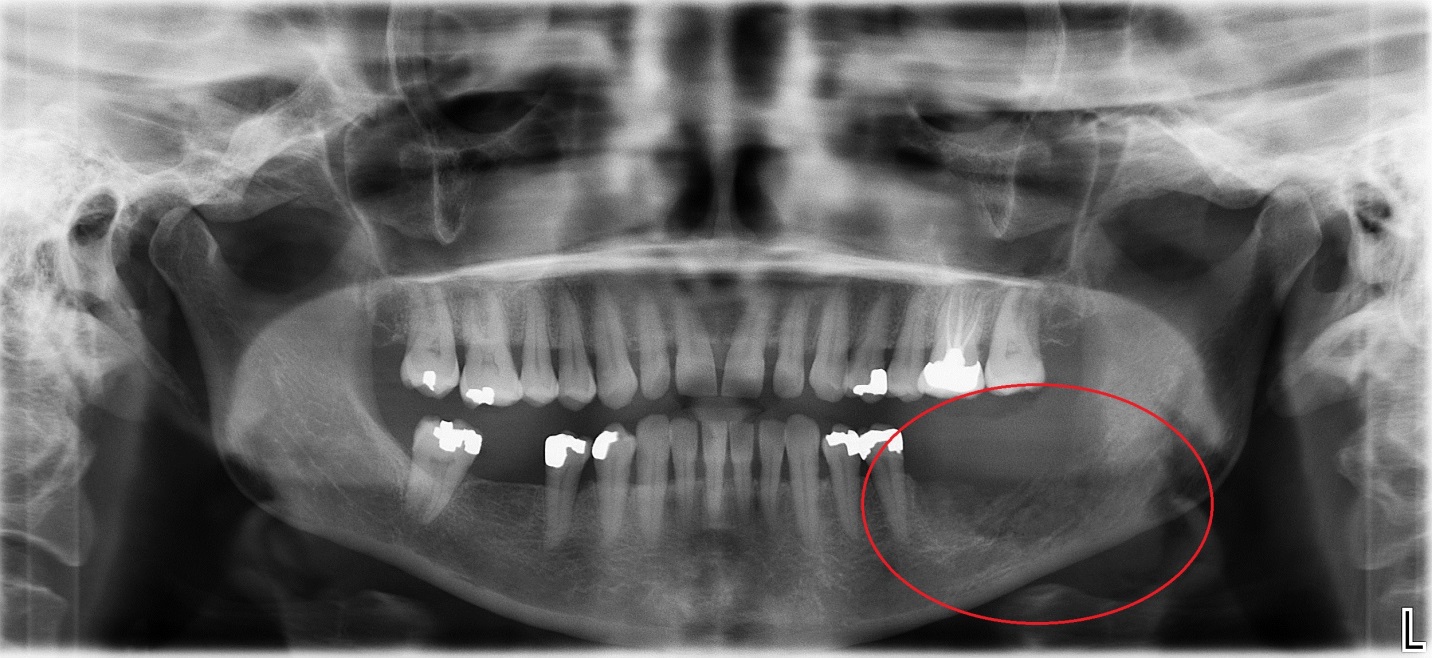

Jaw cancer (ameloblastoma), Xray Stock Image C009/5471 Science

XRay of Dark Resorption in Jaw Bone Duplicate Shadow On Jaw X Ray The cervical spine may be seen in focus on a panoramic radiograph on the most posterior parts of the image. Below, the lesions are divided into cystic and solid. Proper characterization of jaw abnormalities is essential to ensure appropriate patient care and reduce morbidity. Cystic should not be confused with lytic as solid radiolucent lesions can also. Imaging plays a. Shadow On Jaw X Ray.

Jaw cancer (ameloblastoma), Xray Stock Image C009/5471 Science Shadow On Jaw X Ray The cervical spine may be seen in focus on a panoramic radiograph on the most posterior parts of the image. Cystic should not be confused with lytic as solid radiolucent lesions can also. A shadow, or radiolucency, indicates an absence of bone at the tip of a tooth root. This absence of bone is not a normal. Proper characterization of. Shadow On Jaw X Ray.